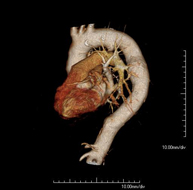

- Angio-TC aorta abdominal  Prueba diagnóstica no invasiva que consiste en el estudio de la arteria aorta abdominal obteniendo imágenes de alta definición anatómica mediante el empleo de un equipo de TC (Tomografía Computarizada) y de contraste yodado. La calidad de las imágenes permite realizar reconstrucciones en 2D y 3D gracias a estaciones de trabajo especializadas en el estudio arterial. Está indicado en aquellos pacientes con enfermedad vascular (aterosclerosis), en aneurismas de aorta, en pacientes con dolor abdominal de posible origen vascular, en estudios pre-quirúrgicos de lesiones adyacentes a la aorta abdominal como "mapa" vascular, etc. La información obtenida de forma no invasiva es indispensable para los pacientes que requieren tratamiento percutáneo o quirúrgico. En aquellos pacientes que solo requieren un seguimiento de las lesiones vasculares, esta técnica es la técnica no invasiva de elección junto con la angio-RM. Prueba diagnóstica no invasiva que consiste en el estudio de la arteria aorta abdominal obteniendo imágenes de alta definición anatómica mediante el empleo de un equipo de TC (Tomografía Computarizada) y de contraste yodado. La calidad de las imágenes permite realizar reconstrucciones en 2D y 3D gracias a estaciones de trabajo especializadas en el estudio arterial. Está indicado en aquellos pacientes con enfermedad vascular (aterosclerosis), en aneurismas de aorta, en pacientes con dolor abdominal de posible origen vascular, en estudios pre-quirúrgicos de lesiones adyacentes a la aorta abdominal como "mapa" vascular, etc. La información obtenida de forma no invasiva es indispensable para los pacientes que requieren tratamiento percutáneo o quirúrgico. En aquellos pacientes que solo requieren un seguimiento de las lesiones vasculares, esta técnica es la técnica no invasiva de elección junto con la angio-RM.

- Angio TC d'aorta abdominal Prova diagnòstica no invasiva que consisteix en l'estudi de l'artèria aorta abdominal amb l'obtenció d'imatges d'alta definició anatòmica mitjançant l'ús d'un equip de TC (Tomografia Computaritzada) i contrast iodat. La qualitat de les imatges permet realitzar reconstruccions en 2D i 3D gràcies a estacions de treball especialitzades en l'estudi arterial. Està indicat en aquells pacients que pateixen malaltia vascular (arteriosclerosi), aneurismes d'aorta, en pacient amb dolor abdominal d'un possible origen vascular, en estudis prequirúrgics de lesions adjacents a l'aorta abdominal com el "mapa" vascular, etc. La informació obtinguda de forma no invasiva és indispensable per als pacients que requereixen tractament percutani o quirúrgic. En aquells pacients que només requereixen un seguiment de les lesions vasculars, aquesta tècnica és la tècnica no invasiva d'elecció juntament amb l'angio RM. Prova diagnòstica no invasiva que consisteix en l'estudi de l'artèria aorta abdominal amb l'obtenció d'imatges d'alta definició anatòmica mitjançant l'ús d'un equip de TC (Tomografia Computaritzada) i contrast iodat. La qualitat de les imatges permet realitzar reconstruccions en 2D i 3D gràcies a estacions de treball especialitzades en l'estudi arterial. Està indicat en aquells pacients que pateixen malaltia vascular (arteriosclerosi), aneurismes d'aorta, en pacient amb dolor abdominal d'un possible origen vascular, en estudis prequirúrgics de lesions adjacents a l'aorta abdominal com el "mapa" vascular, etc. La informació obtinguda de forma no invasiva és indispensable per als pacients que requereixen tractament percutani o quirúrgic. En aquells pacients que només requereixen un seguiment de les lesions vasculars, aquesta tècnica és la tècnica no invasiva d'elecció juntament amb l'angio RM.